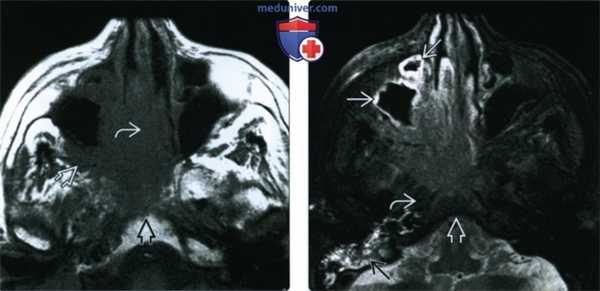

(Слева) При аксиальной МРТ Т1 определяется ПКР полости носа с вовлечением носовой перегородки, распространением кнаружи в крылонебную ямку и кзади в носоглотку, к основанию черепа.

(Справа) При аксиальной МРТ Т2 FS визуализируются края опухоли, отличной от утолщенной слизистой оболочки верхнечелюстной пазухи, превертебральных мышц и костного мозга ската с подавленным сигналом. Утолщение слизистой оболочки сосцевидного отростка связано с обструкцией евстахиевой трубы.